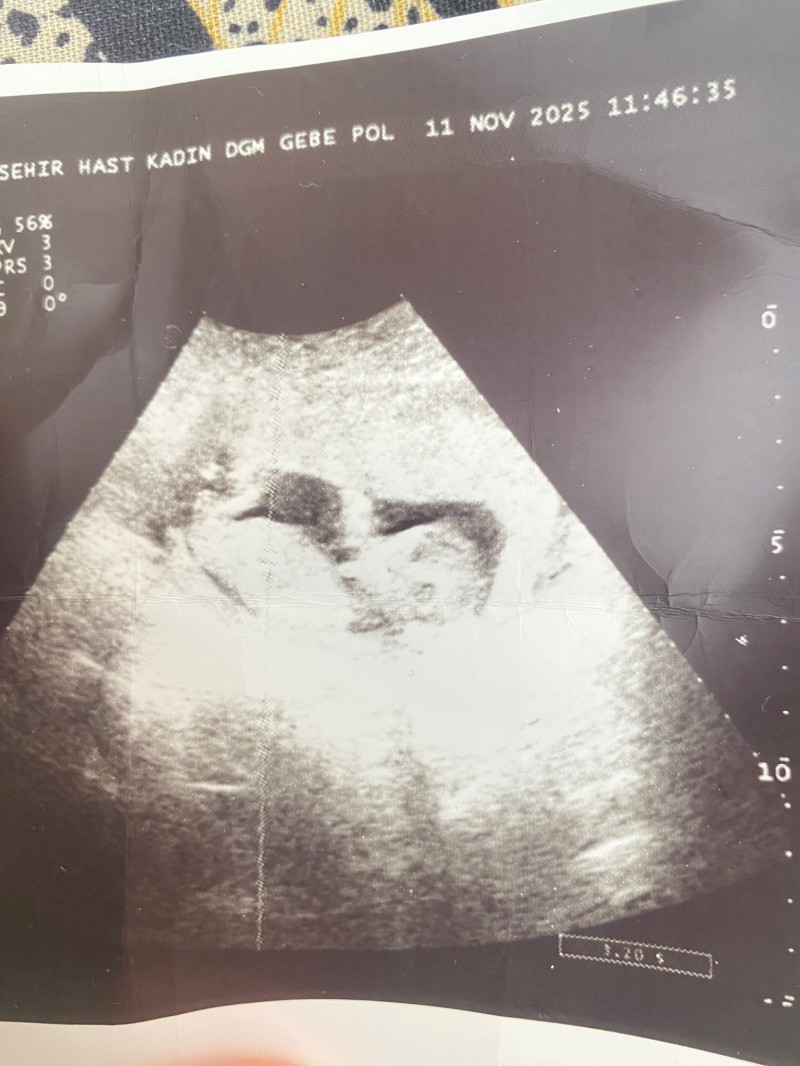

2.yeğenim geliyor ama bir türlü göstermedi cinsiyeti öğrenemedik merak ediyoruz iyi bileenler vardır burda güveniyorum size hadi yorumlayın kızçe istiyorum ben ama bilmiyorum inşallah 🥰

Kız gibi sanki.

Göstermeyince kiz oluyor

Bana kiz gibi geldi

Kafası kızların kafasına benziyor.

Birde benim üçüncü kızım doğuma kadar göstermedi. Ankaralı bir doktor genelde göstermeyenler kızdır  yüzde 90 demişti.